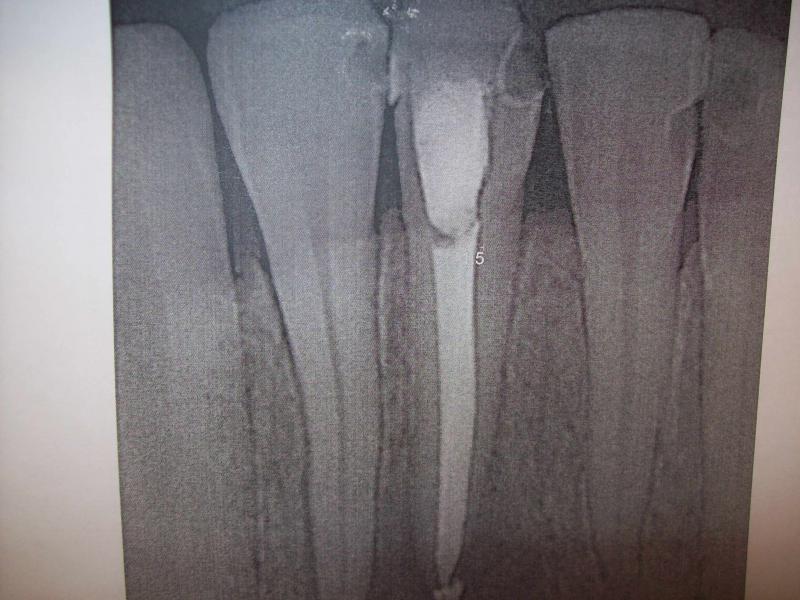

DR JET LOVES ROOT CANALS

General Dentist,  Performs Root Canals ONLY - Microscope Trained Dentist

"DR. JET'S MISSION IS TO PERFORM  ROOT CANALS FOR A REDUCED FEE USING THE LATEST TECHNOLOGY  AND TECHNIQUES TO SERVICE THE MANY PEOPLE WHO ARE UNINSURED OR UNDER-INSURED GIVING EVERYONE AN OPPORTUNITY TO SAVE THEIR TOOTH!"

**PLEASE BE AWARE THAT  A ROOT CANAL IS AN ATTEMPT TO SAVE YOUR ALREADY DAMAGED TOOTH.  THERE IS NO GUARANTEE THAT ANY TOOTH CAN BE SAVED BUT DR JET WILL DO HIS BEST TO HELP YOU. THE OTHER OPTION IS TO EXTRACT YOUR TOOTH